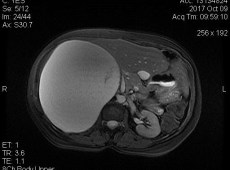

Straordinario intervento al Civico di Palermo: rimosso un tumore di 22 kg

“Si tratta di una performance chirurgica di elevata complessità per l’imponente volume della neoplasia, le criticità anatomiche specifiche del caso ed il conseguente maggior rischio intraoperatorio, eseguita presso la Chirurgia […]